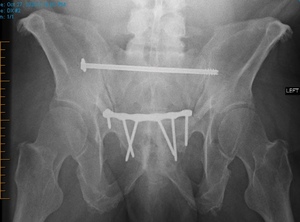

Posterior pelvic ring fixation with SI or TITS fixation is a well-accepted, successful means of fixation with good outcomes. Despite its widespread utilization, a paucity of publications exists on the indications and results of implant removal (Abumi et al. 2000; Culemann et al. 2004; Gänsslen, Hüfner, and Krettek 2006; Chip Routt, Simonian, and Mills 1997). Several case reports have demonstrated the proximity of neurovascular structures to these screws and demonstrated the possible risks associated with screw removal (Ebraheim et al. 1997; Mirkovic et al. 1991; Chip Routt, Simonian, and Mills 1997; Templeman et al. 1996). Figure 3 presents a diagram showing the proximity of neurovascular structures most likely to be damaged during placement or removal surgery.